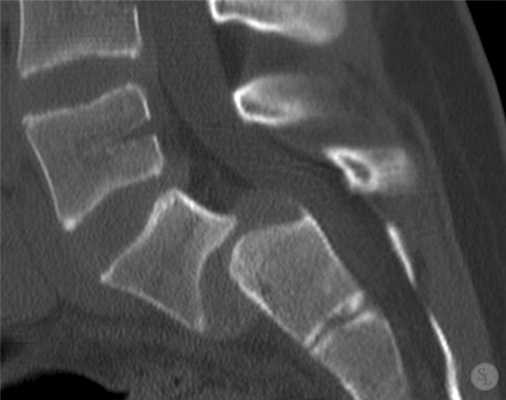

3 месяца после операции.